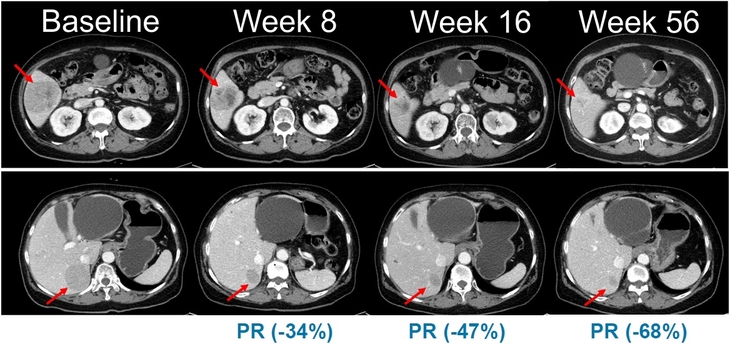

▲NRAS 돌연변이 흑색종 환자를 대상으로 진행된 벨바라페닙과 코비메티닙 병용요법 임상시험에서 시간 경과에 따른 병변 변화가 관찰된 복부 CT 영상. 사진=한미약품